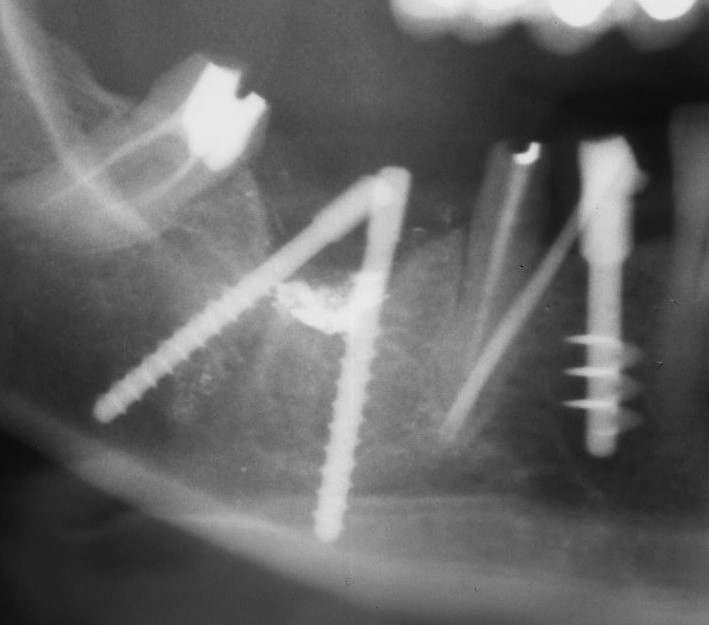

Una delle critiche che si fa all’implantologia italiana riguarda l’utilizzo di bipodi e tripodi e delle forche che si creano. L’implantologia di scuola italiana realizza questo genere di unità implantari da sempre e lo fa proprio perché l’esperienza clinica di centinaia di migliaia di casi spalmati su centinaia di operatori ha permesso di appurare che le forche sotto elementi implantari non sono assimilabili a quelle sotto elementi naturali, come appare ovvio, dato che le forche sotto unità implantari non possono determinare patologie parodontali per la mancanza di un elemento fondamentale: il tessuto parodontale. Il caso riportato è emblematico, rappresentando le condizioni peggiori in cui una forca implantare si possa trovare: sospesa nell’alveolo chirurgico fresco in caso di impianti postestrattivi.

Nella prima foto si vedono gli impianti inseriti contestualmente alla rimozione di un impianto sepolto colpito da grave perimplantite, nella seconda il controllo a sette anni di distanza che dimostra non solo che non c’è stata perdita ossea perimplantare, ma addirittura un fenomeno osteoriparativo che non solo ha riempito il difetto osseo lasciato dal precedente impianto sepolto rimosso, ma addirittura lo ha superato dimostrando un lieve accrescimento verticale